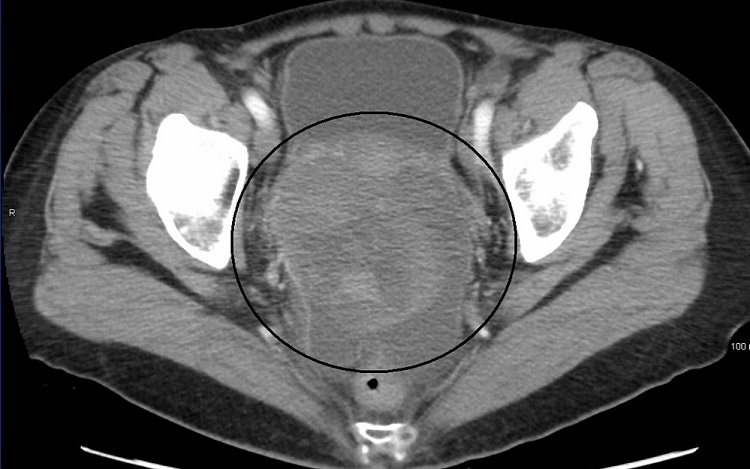

Clinical picture of diagnosis

During the early stages of ovarian cancer, symptoms may be absent or minimal. However, when symptoms occur, they may initially include pelvic discomfort or pressure, unexpected vaginal bleeding, abdominal or back pain, bloating, and changes in bowel or urination patterns.